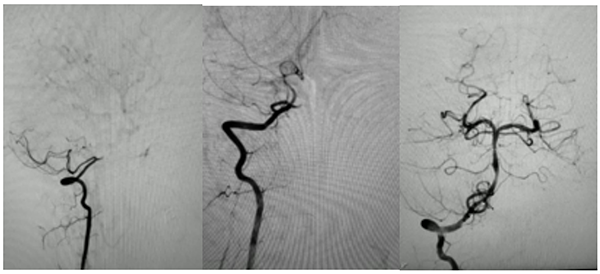

经评估后结合患者病史,考虑为基底动脉闭塞所致的脑干梗死,神经内科尹榕主任带领卒中团队为减少穿刺并发症,提高患儿舒适度及依从性,选择经桡动脉入路,为患儿完善脑血管造影明确基底动脉起始部闭塞,经抽吸、支架取栓后发现患者为动脉夹层所致血管闭塞,前向血流无法维持,经与家属沟通同意后置入基底动脉支架维持前向血流通畅。手术过程顺利,术后患儿转入PICU二部,并联合卒中团队、神经重症团队、神经康复团队共同进行术后综合管理。